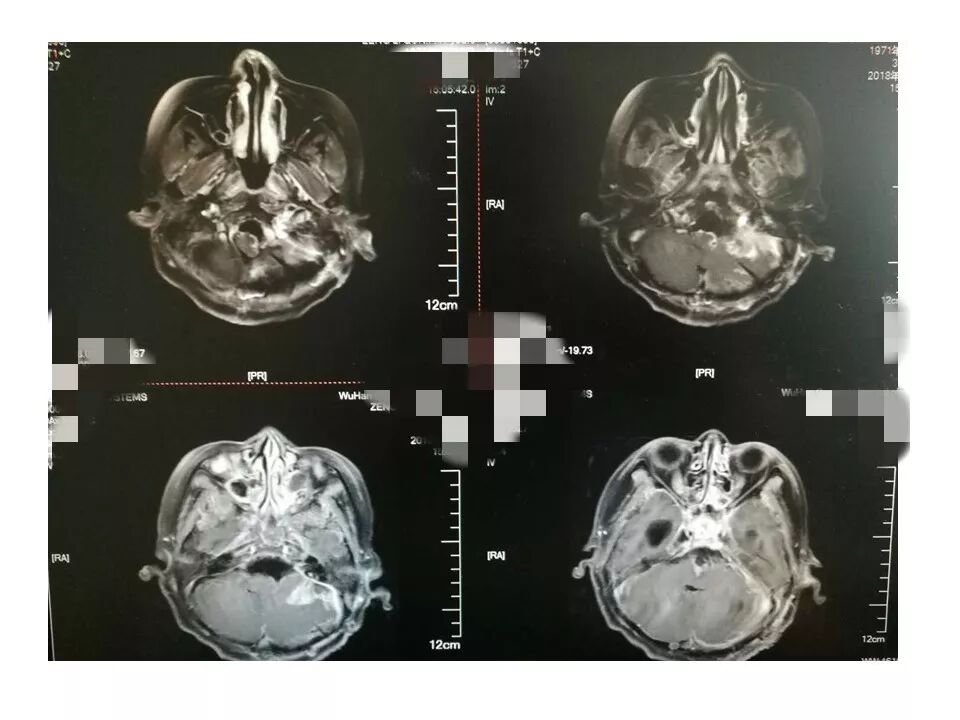

今天为大家分享的是《贝朗时间》第三十八期,由中国人民解放军武汉总医院神经外科副主任姚国杰教授带来的:远外侧入路全斜坡巨大脑膜瘤显微手术1例,欢迎阅读、分享!

远外侧入路全斜坡巨大脑膜瘤显微手术1例